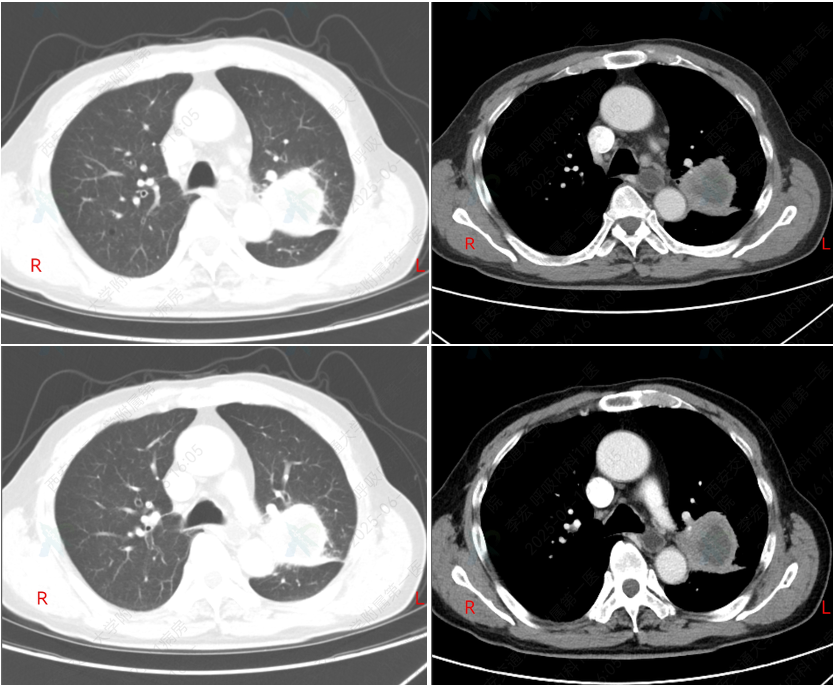

2025-1-17 首次用药后,胸部CT结果如下,提示病灶明显缩小;

图7 2024-12-6(左)对比2025-01-17(右)胸部CT

2025-04-26 用药5周期后,胸部CT结果如下所示,疗效评估为PR

图8 2024-12-6(左)对比2025-04-26(右)胸部CT

2025-6-16 用药7周期后,胸部CT结果如下所示,疗效评估为PR

图9 2024-12-6(左)对比2025-06-16(右)胸部CT

截止最新随访时间(2025-09-12),该患者持续PR,目前仍在接受“依沃西单抗联合化疗”方案治疗。

本病例中患者因“间断咳嗽2月余,痰中带血1天”入院,经系列检查后初步诊断为左肺鳞癌T3N3M0 IIIC期,并伴有慢性阻塞性肺疾病等多种疾病,肺功能差(GOLD评分3级),经综合评估后一线治疗给予该患者依沃西单抗联合化疗方案。患者治疗1周期后迅速缩瘤,治疗9周期期间持续PR。同时,治疗期间未出现明显治疗相关不良事件(TRAEs)。目前,患者仍接受依沃西单抗联合化疗治疗,已持续治疗10个月,仍在随访中。